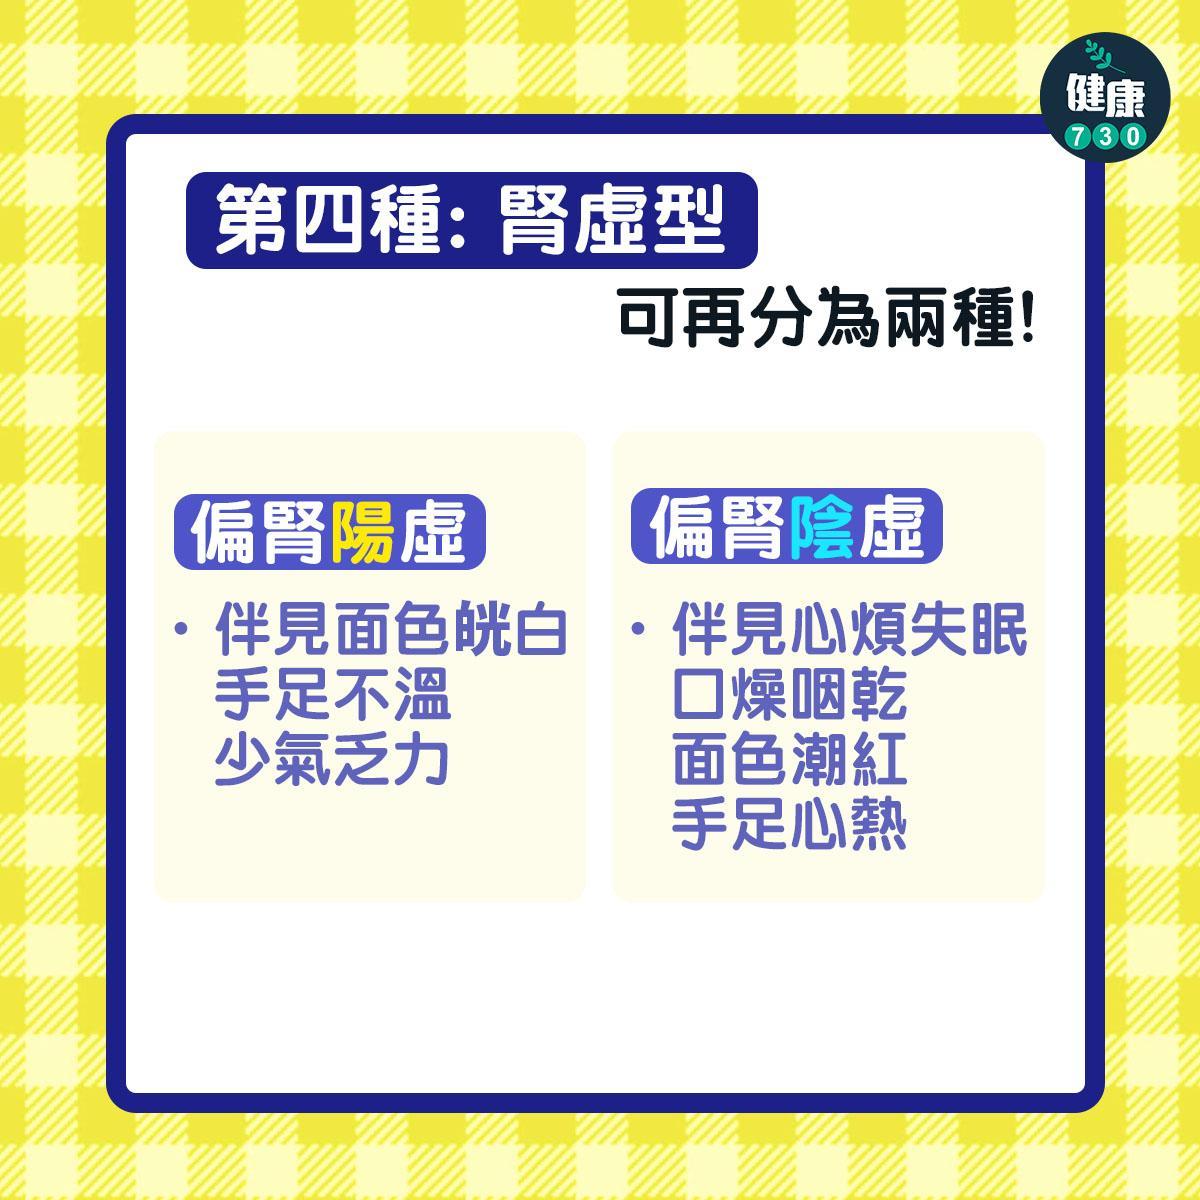

兩類腰骨痛

腰骨痛可以分為兩大類,一是由神經問題引起,另一個是肌肉或關節相關的。神經問題大多興椎間盤問題,或者神經根從脊椎走了出來,出現擠壓而疼痛。這些腰骨痛就需要找醫生診斷而作出適切治療。